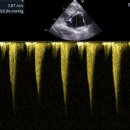

동물메디컬센터 ​ 고양이 심장병이란? 고양이 심장병 증상은 호흡곤란, 기침, 기력저하, 식욕 부진 등이 있다. ​ 특히 HCM (비대성심근증성)이 고양이 심장병 중 제일 흔한 질병이다. ​ 심장 근육이 비정상적으로 두꺼워지는 질환을 말한다. ​ 나이, 품종, 성별 상관없이 발생할 수 있지만 유전 영향이 크기 때문에 *일부...